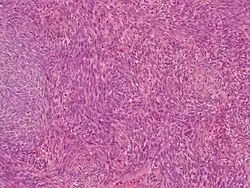

![]() Mięsak maziówkowy, obraz mikroskopowy | |

Mięsak maziówkowy jest definiowany jako guz zbudowany z wrzecionowatych komórek wykazujących różnego stopnia zróżnicowanie w kierunku tkanki nabłonkowej wykazując typową translokację t(X;18)(p11;q11)[7]. Nowotwór wbrew swojej nazwie nie jest związany z błoną maziową[1]. Mimo że mikroskopowo przypomina błonę maziową, to nie ma dowodów na wywodzenie się z błony maziowej czy różnicowanie się w jej kierunku[1].

Mięsak maziówkowy składa się z dwóch komponentów odmiennych morfologicznie komórek – komórek wrzecionowatych przypominających włókniakomięsak oraz komórek nabłonkopodobnych podobnych do raka[2][31]. Na podstawie udziału obu komponentów oraz stopnia zróżnicowania wyróżnia się dwa warianty histopatologiczne mięsaka maziówkowego – dwufazowy (biphasic) oraz jednofazowy (monophasic). Dwufazowy mięsak maziówkowy zawiera komponent z komórek wrzecionowatych (jednofazowy włóknisty) oraz komponent zbudowany z komórek nabłonkopodobnych wymieszanych w różnych proporcjach. W jednofazowym mięsaku maziówkowym wyróżnia się warianty z komórek wrzecionowatych i z komórek nabłonkopodobnych[1][2][21][32]. Wariant niskozróżnicowany właściwie nie jest uważany za osobny podtyp mięsaka maziówkowego, a raczej za następstwo progresji wariantu dwufazowego lub jednofazowego[1].

Mikroskopowo mięsak maziówkowy dwufazowy zawiera współistniejące dwie morfologicznie odmienne komponenty z komórek wrzecionowatych i nabłonkopodobnych o różnych wzajemnych proporcjach w tworzeniu utkania mięsaka[2].

Komponenta z komórek nabłonkopodobnych jest zbudowana z komórek od sześciennego do walcowatego kształtu, o dużym owalnym lub okrągłym jądrze z bogatą bladą cytoplazmą. Komórki tworzą gniazda, sznury lub struktury gruczołowe[7][2]. Czasem komórki o płaskim lub sześciennym kształcie pokrywają struktury brodawkowate lub kosmkowate z rdzeniem z komórek wrzecionowatych[2]. Możliwa jest metaplazja płaskonabłonkowa[7].

Komponentę z komórek wrzecionowatych budują jednolite komórki o wrzecionowatym kształcie z ubogą cytoplazmą, z małym, okrągłym jądrem komórkowym, granice komórek są niewyraźne, komórki są ułożone w gęste, równoległe arkusze, które przypominają utkanie włókniakomięsaka, zrąb zwykle jest skąpy[35][7]. Mogą występować obszary ubogokomórkowe wykazujące obszary hialinizacji, zwyrodnienia śluzowego oraz ogniskowe zwapnienia[35]. Guzy wykazują różny stopień unaczynienia, u części chorych mogą występować poszerzenia przestrzeni naczyniowych przypominające obłoniaka (hemangiopericytoma)[36]. Może występować naciek z mastocytów, który jest bardziej nasilony w komponencie z komórek wrzecionowatych[36]. Zarówno w komponencie z komórek nabłonkopodobnych, jak i wrzecionowatych występują figury mitotyczne, przy czym liczne figury mitotyczne towarzyszą wariantowi niskozróżnicowanemu[35]. Zwapnienia z lub bez tworzenia osteoidu mogą występować w 20–33% przypadków[37][35], zwapnienia mogą być niewielkie jako liczne, drobne, sferyczne konkrecje, ale również mogą zajmować znaczną objętość guza[35]. W części przypadków osteoid może naśladować kostniakomięsaka[37].